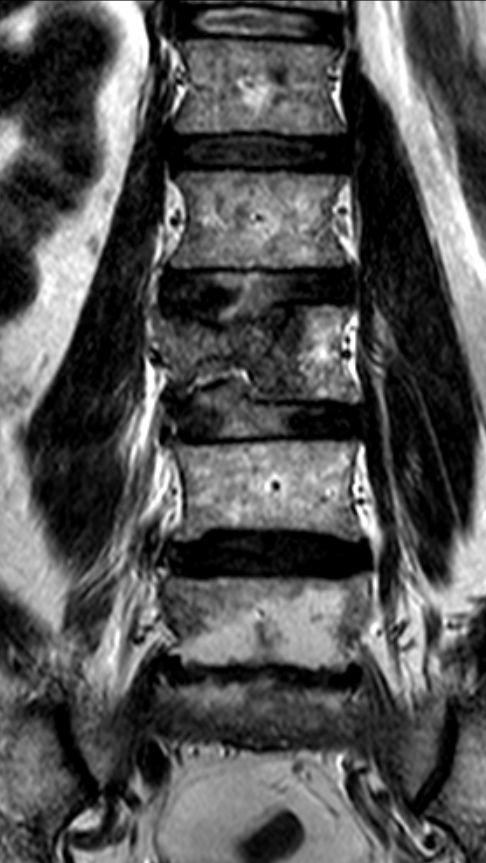

57-jähriger Mann mit einem Nierenzellkarzinom links und Lymphknotenmetastasen.![]() | |